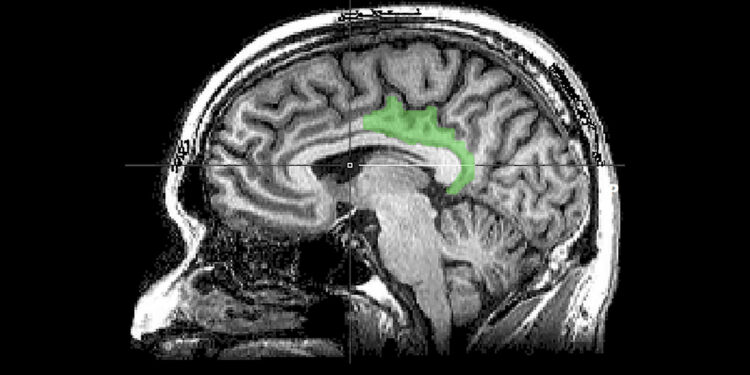

Este tipo de recuerdos parece involucrar un área diferente del cerebro: la corteza cingulada posterior, o CCP, que suele estar implicada en el pensamiento dirigido internamente, como la introspección o la ensoñación diurna. Cuanto más graves fueran los síntomas de TEPT de la persona analizada, más actividad aparecía en el CCP.

Lo sorprendente de este hallazgo es que a la CCP no se la conoce como región de memoria, sino como que está dedicada al «procesamiento de la experiencia interna», observó Schiller.

Gran parte de la investigación sobre el trastorno de estrés postraumático se ha centrado en la amígdala cerebral, el centro de detección del estrés del cerebro, y el hipocampo, subrayó Lanius. La corteza cingulada posterior está “realmente involucrada en revivir recuerdos” y en buscar la relevancia personal, lo autorreferencial, cosa que puede explicar por qué un recordatorio sensorial puede causar miedo o pánico abrumadores.